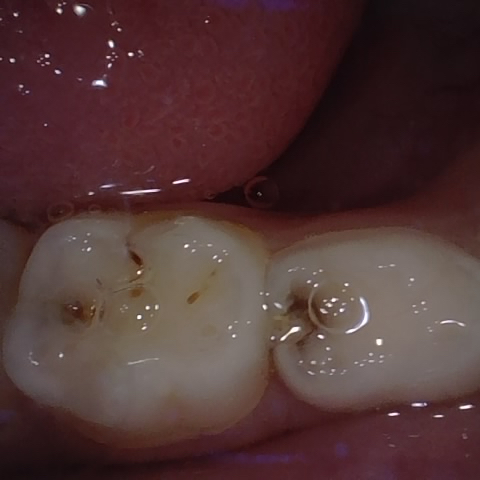

Annotated as "Bad"

Original Image Rendering Image